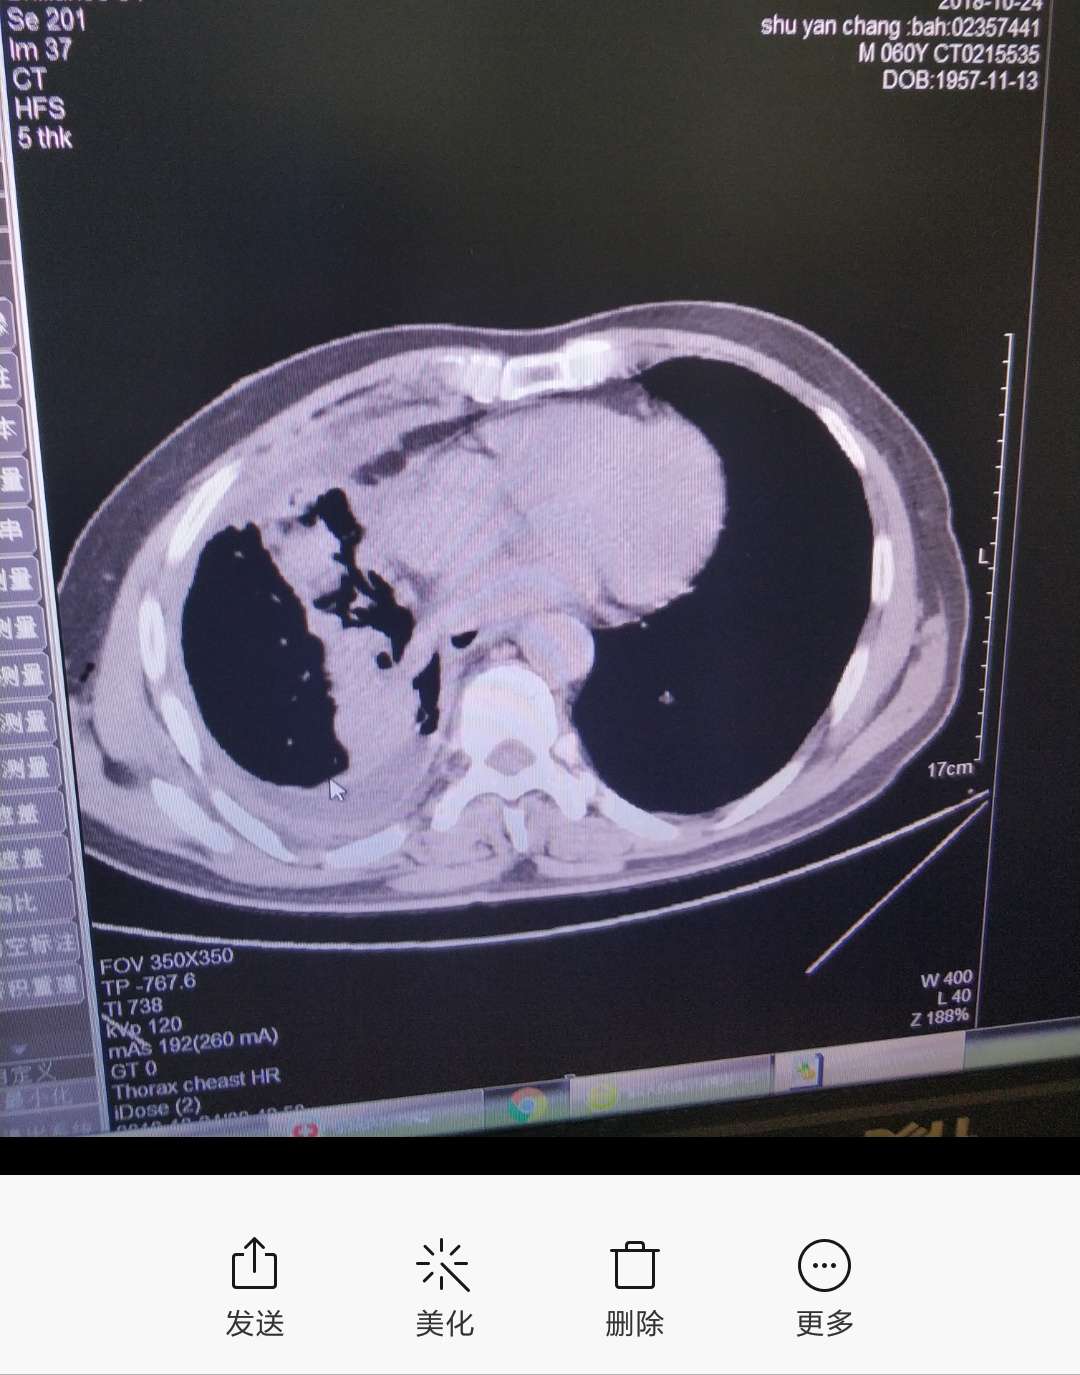

晚上好,我爸爸胸水控制不住周一转到浙二滨江呼吸科就诊,19突变易瑞沙吃2个月时间,昨天CT做出来医生说相比较上次9月18日肿瘤还大了而且有新的,医生建议易瑞沙可能耐药才2个月时间,易瑞沙没效果,前天还咳血了15ml鲜红色,今天中午又咳血了一口,医生建议化疗药卡铂+培美曲塞,或者做其他有靶向药的全基因检测,这两天开始吃善存维生素片,+白蛋白偏低自费打了白蛋白针和香菇多糖,我这两天压力很大,不知道该怎么办好,希望能够得到您的一些建议,谢谢,谢谢